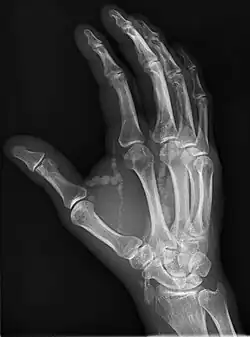

| Hand radiograph showing tumoral calcinosis, PA radiograph of the right hand showing tumoral calcinosis-like metastatic calcification in a patient on dialysis. Dialysis alters calcium phosphate product (>70). Idiopathic tumoral calcinosis is autosomal dominant and is not associated with dialysis. Note the premature arterial calcification which is a clue that this is a renal patient. Vascular calcification contributes to an increase in morbidity. |

Tumoral calcinosis is a rare condition in which there is calcium deposition in the soft tissue in periarticular location, around joints, outside the joint capsule.[1] They are frequently (0.5–3%) seen in patients undergoing renal dialysis. Clinically also known as hyperphosphatemic familial tumoral calcinosis (HFTC), is often caused by genetic mutations in genes that regulate phosphate physiology in the body (leading to too much phosphate (hyperphosphatemia)). Best described genes that harbour mutations in humans are FGF-23,[2] Klotho (KL),[3] or GALNT3.[4] A zebrafish animal model with reduced GALNT3 expression also showed HFTC-like phenotype,[5] indicating an evolutionary conserved mechanism that is involved in developing tumoral calcinosis.

The name indicates calcinosis (calcium deposition) which resembles tumor (like a new growth). They are not true neoplasms – they don't have dividing cells. They are just deposition of inorganic calcium with serum exudate. Children and adolescents (6 to 25 years) are the most commonly affected. The symptom that the accumulations cause is not pain but swelling around joints. They have propensity to enlarge progressively and ulcerate the overlying skin and extrude. They are most common around shoulders, hips and elbows. Laboratory evaluation reveal normal serum calcium levels and hyperphosphatemia. Rarely ALP (alkaline phosphatase – an enzyme active at sites of bone formation) may be elevated. Treatment is normalization of serum phosphate levels and resection of lesions. Surgical removal should be complete and if part of it is left, recurrence is likely to occur. Cutting through the excised calcium deposition reveals semifluid calcium suspension in albumin encapsulated by fibrous tissue.